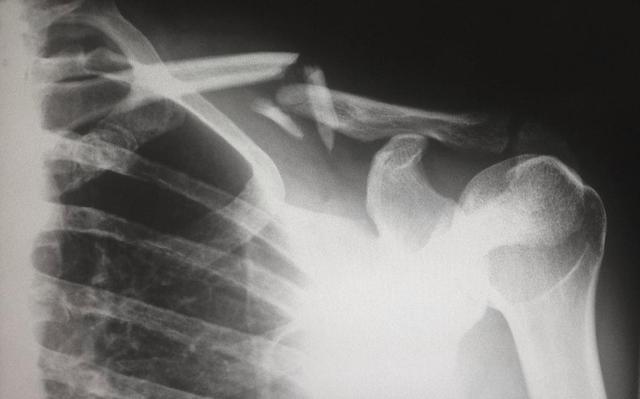

一提到骨质疏松这个问题,其实并不如大家想的那般稀少,相反在中老年人群,尤其是四十岁以后的人群中,骨密度较低者占比已达35%左右,而知道自己存在骨密度较低问题,也即骨质疏松情况者,却不到1%